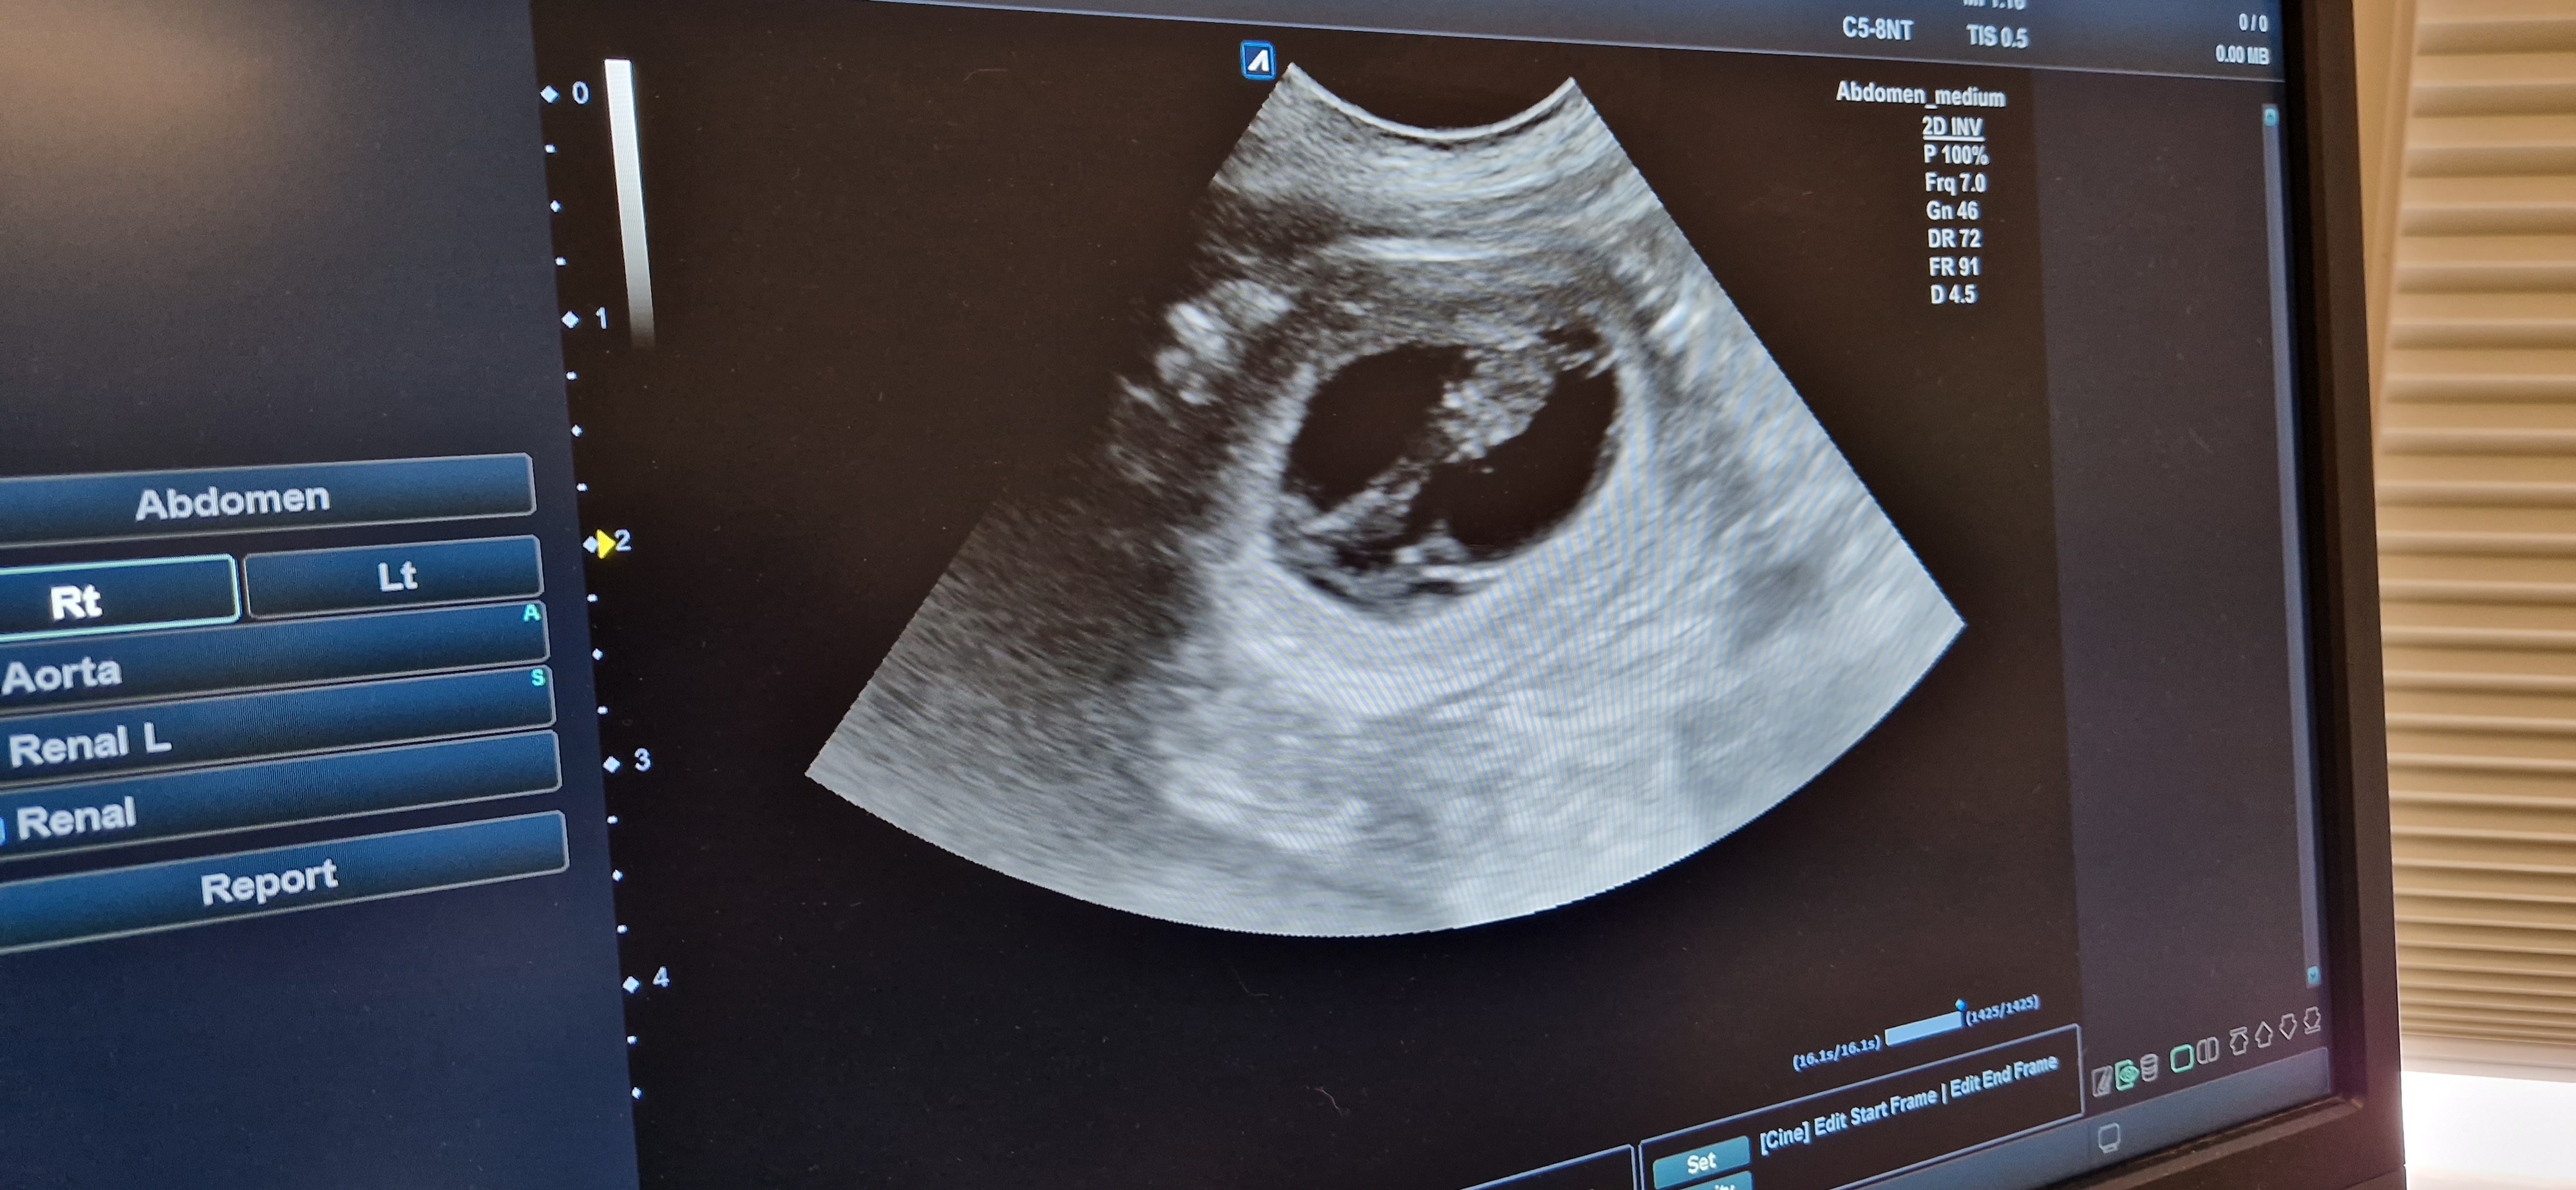

I dag var time bestilt hos verinærene på Norderhov og Anette kunne vise oss små hjerter som slår. Så ihvertfall 3 på en gang❤️

Så nå er det bare å vente i spenning til slutten av april og se hvor mange magen skjuler🥰